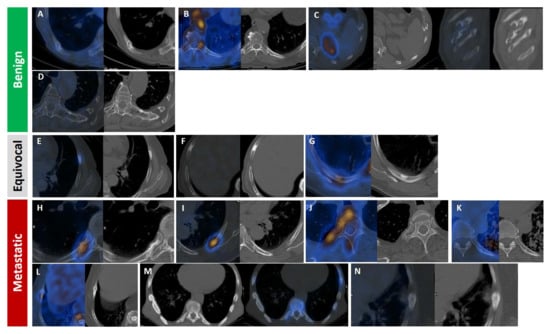

Pleuro-Pulmonary Extramedullary Plasmacytomas in Multiple Myeloma: A 15-Year Experience from a Tertiary Center

Sorina Badelita, Sinziana Barbu, Camelia Dobrea, Cerasela Jardan, Monica Popescu, Codruta Delia Popa, Claudia Toma, Larisa Zidaru, Mihai Emanuel Himcinschi, Horia Mihail Sandu, Didona Vasilache, Adelina Vlad and Daniel Coriu

Background/Objectives: Extramedullary involvement in multiple myeloma represents an aggressive disease phenotype, associated with reduced survival and an unfavorable prognosis. Thoracic manifestations are rare and remain poorly characterized in the literature. Methods: We conducted a retrospective, single-center study at the Fundeni Clinical Institute, including patients diagnosed with multiple myeloma between February 2010 and February 2025. The study cohort consisted of 34 patients with infiltration of the pulmonary parenchyma, pleura, or the presence of myelomatous pleural effusion. Diagnosis was confirmed using a combination of imaging modalities (computed tomography or magnetic resonance imaging), cytological examination, immunophenotyping, and histopathological confirmation whenever feasible. Results: Out of a total of 2012 patients with multiple myeloma, the incidence of pleuro-pulmonary extramedullary involvement was 1.6%. The median age at diagnosis was 58 years. Pleuro-pulmonary disease was present at initial diagnosis in 26.5% of cases, while 73.5% developed it at relapse. The most common presentation involved combined pleural involvement and myelomatous effusion (70.6%). Adverse prognostic markers included elevated β2-microglobulin levels (in over 80% of cases) and increased lactate dehydrogenase (LDH) in approximately 50%. Cytogenetic abnormalities such as del(17p), t(4;14), t(14;16), t(11;14), and 1q gain were identified. The median overall survival (OS) from the diagnosis of pleuro-pulmonary extramedullary disease was 16 months, with a 2-year survival rate of 25%. No patient survived beyond 5 years. The median progression-free survival (PFS) was 9 months. Conclusions: Our findings confirm the aggressive clinical course and poor prognosis of these disease manifestations, mainly when they occur at relapse. In the absence of standardized treatment guidelines, individualizing therapy and accessing novel strategies may be essential for improving patient survival.

Full article